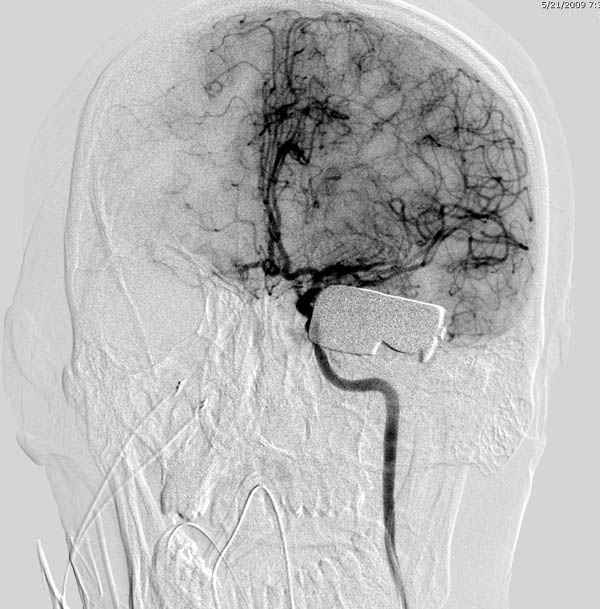

В своих выступлениях я рассказывал, что наши центры в мирное время по пенетрирующим травмам не уступает Ираку или Афганстану, и вот недавно к нам поступила больная 22 лет, травма "ножом в глаз" от бывшей подруги нынешнего "бой френда".

При поступлении в сознании, жаловалась на неприятные ощущения в глазнице.

По протоколу сделаны все необходимые исследования: рентген, ангиограмма с 3Д реконструкцией, где обнаружили что все жизненно важные сосуды не задеты, даже некоторые "сидят" изгибаясь на ноже.

Одним махом нож удалить не удалось, пришлось раскачать и потом двумя руками удалили нож. Рана без кровотечения, обработана и зашита.